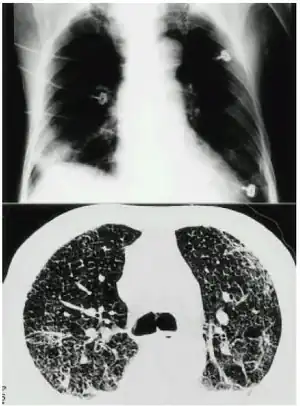

a,b)Mercury inhalation poisoning and acute lung injury-chest images

• CT scan of chest

• X-ray of the chest